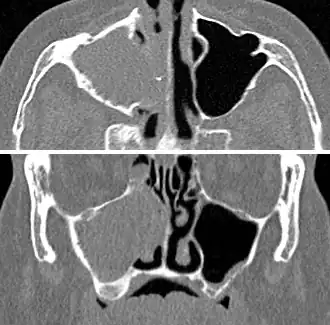

For sinusitis lasting more than 12 weeks, a CT scan is recommended.[66] On a CT scan, acute sinus secretions have a radiodensity of 10 to 25 Hounsfield units (HU). In a more chronic state, they become more viscous, with a radiodensity of 30 to 60 HU.[69]

-

CT of chronic sinusitis -

CT scan of chronic sinusitis, showing a filled right maxillary sinus with sclerotic thickened bone -